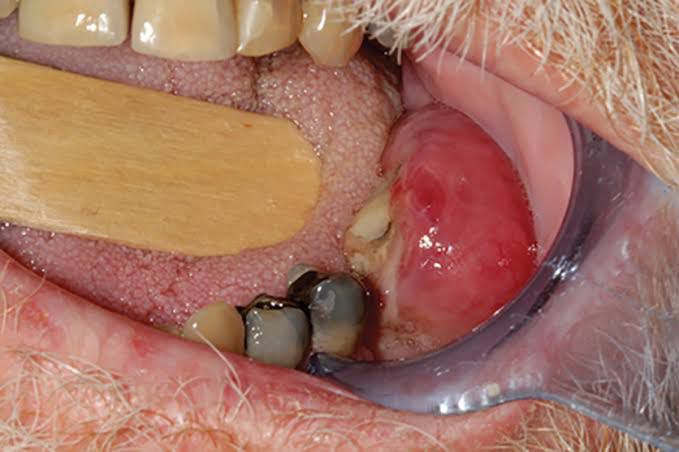

Cancer of the gums. It is often associated with the use of smokeless (chewing) tobacco. Diagnosis is by observation and confirmed by biopsy. Treatment may include radiation, chemotherapy, and surgery.